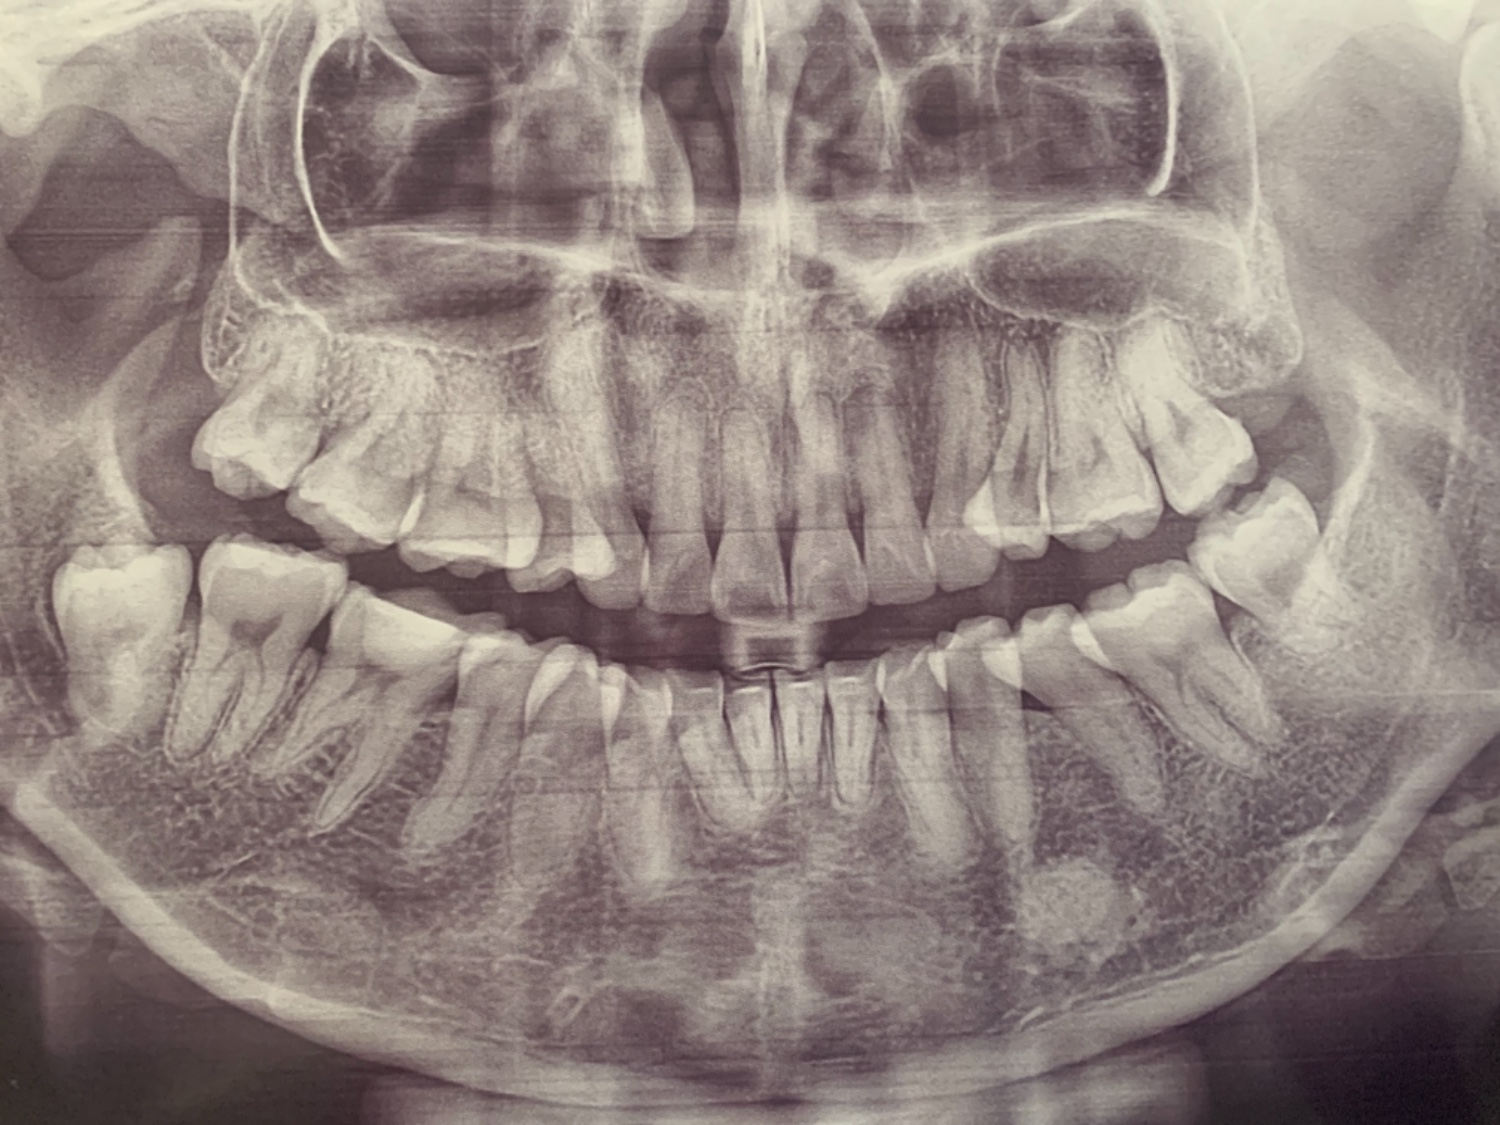

รากฟันแบบนี้ สามารถจัดฟันได้ไหม(มีรูป)

คือเราเคยจัดฟันมาแล้ว แล้วไม่ได้ใส่รี ตอนนี้กลับมาเหยินอีก เลยอยากจัดฟันอีกรอบ รากฟันแบบนี้เรายังสามารถจัดได้อีกไหม